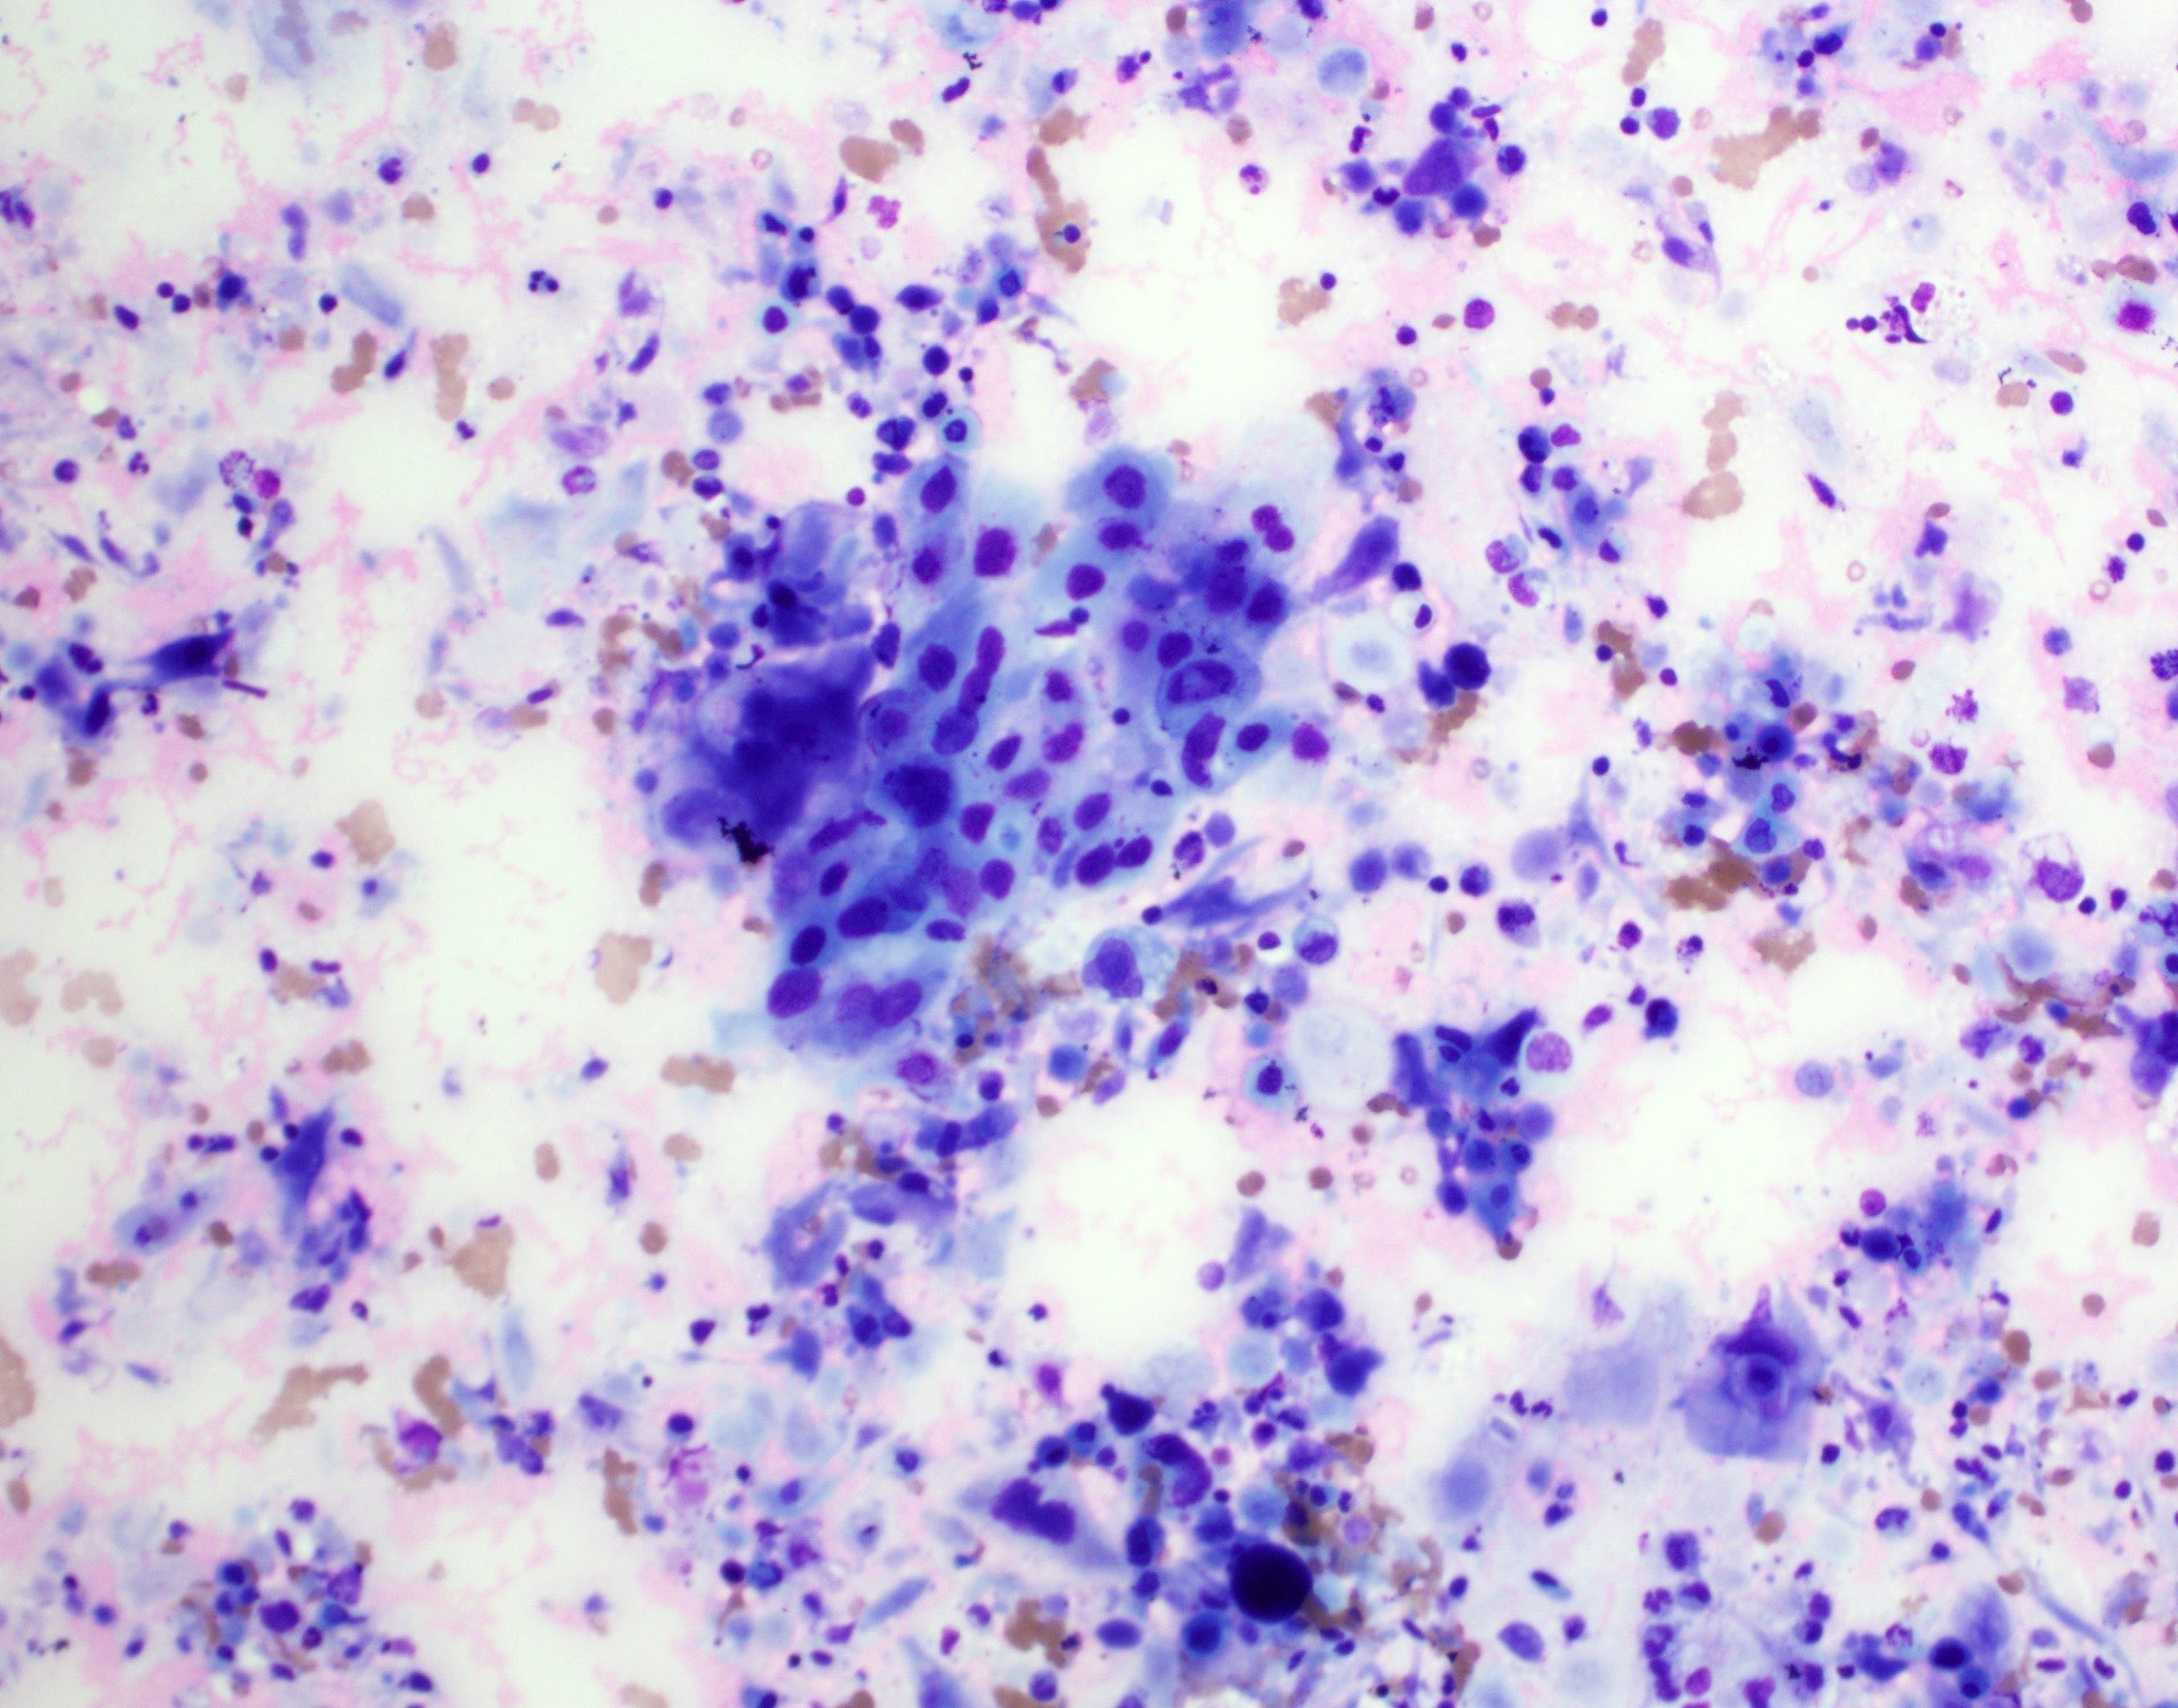

Cytology description

- Role of cytology only in investigation of regional or distant metastases

- Appearance depends on type and differentiation

- Conventional squamous cell carcinoma shows sheets and small clusters of large polygonal malignant cells with intercellular bridges and cytoplasmic or extracellular eosinophilic keratin

Cytology images